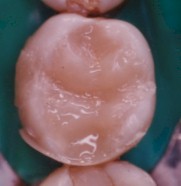

El resultado final

es una restauración excepcionalmente estética, con una anatomía capas de

devolver la función y reintregar a esta pieza dentaria al sistema masticatorio.

(foto 11)

FOTO

11 |

12 |